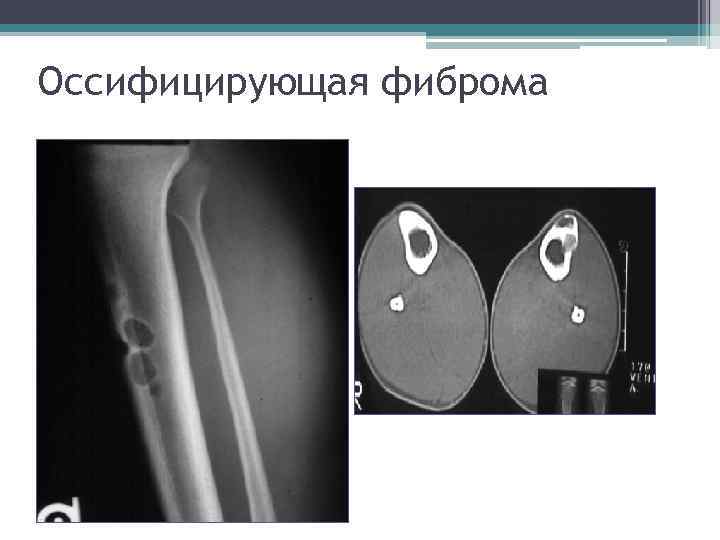

Неостеогенная (неоссифицирующая) фиброма • Пораженный участок располагается эксцентрически. • Возникает из костного мозга. • Локализуется она обычно в верхней или нижней трети длинных трубчатых костей.

Оссифицирующая фиброма